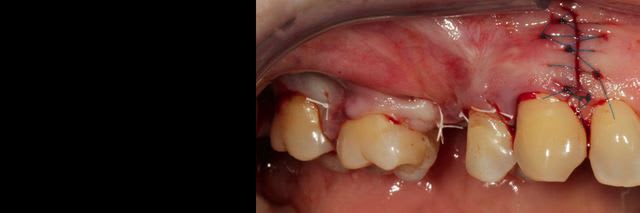

Bon j'ai extrait la dent et maintenant y a un gros trou.

J'ai décidé de réaliser un lambeau déplacé latéralement associé à un conjonctif enfoui le jour de l'extraction afin d'avoir des tissus mous de meilleure qualité pour la greffe, ci joint les photos à 6 semaines.